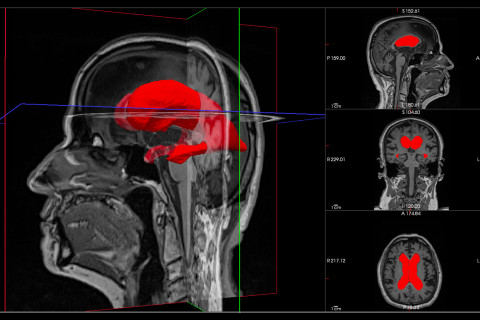

Enlarged lateral ventricles of an idiopathic normal pressure hydrocephalus patient.

In this study, researchers used brain scans from 170 patients with iNPH. Using advanced 3D imaging and machine learning, they quantified and analysed the geometric features of the brain’s lateral ventricles to predict the success of surgical intervention. They found that a geometric marker, asphericity, was strongly associated with better surgical outcomes.